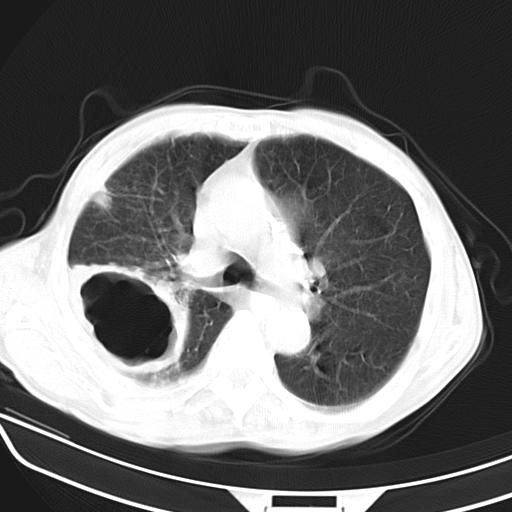

男,70,发烧咳嗽咳痰10余天,查痰结核菌阴性。否认以前有肺病史。治疗10天后症状减轻。 img]/upload/forum/2009/12/302117469692.jpg[/img]

影像所见:右上肺见一巨大厚壁空洞,内壁欠光整,右上肺广泛斑片状、大片状模糊阴影。

影像所见:右上肺见一巨大厚壁空洞,并见分隔,内壁欠光整,右上肺广泛斑片状、大片状磨玻璃阴影。